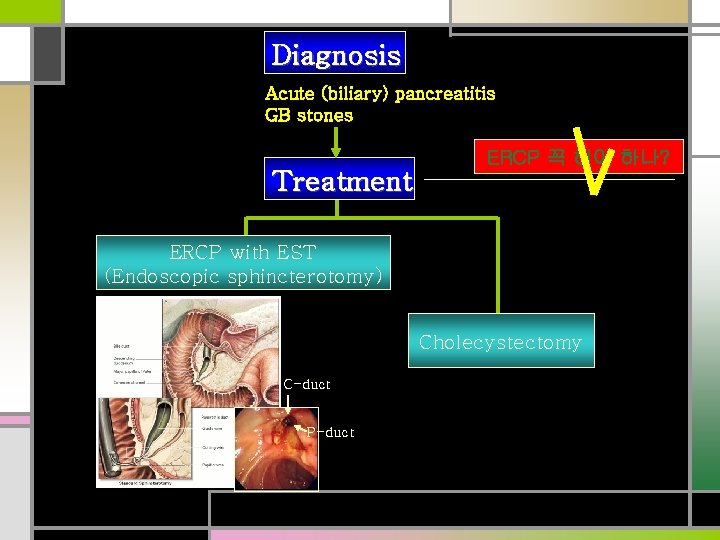

Diagnosis Acute (biliary) pancreatitis GB stones Treatment ERCP 꼭 해야 하나? ERCP with EST (Endoscopic sphincterotomy) Cholecystectomy C-duct P-duct